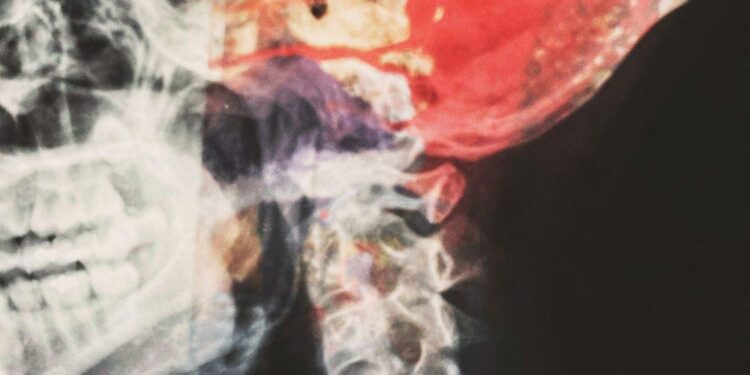

Inside the brain there are hollow spaces called ventricles. The ventricles are usually filled with cerebrospinal fluid. From the ventricles, CSF moves through a series of pathways. Eventually, the fluid surrounds the brain and spinal cord.

It could be that the cerebrospinal fluid isn’t properly absorbed into the bloodstream, or there is a blockage in the pathway that the fluid usually flows through. When that happens, it can lead to a condition called hydrocephalus, where the extra CSF fluid puts pressure on the brain.

Furthermore, there is extra cerebrospinal fluid between the brain and spinal cord, and it can damage the brain. This can affect the memory area of the brain among others. In extreme cases, it can even be life-threatening. Hydrocephalus can also affect kids causing their heads to enlarge, and lead to developmental delays.